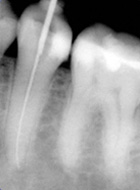

Ist der Zahnnerv durch Karies oder seltener, durch einen Unfall so geschädigt, dass er entfernt werden muss, wird eine Wurzelbehandlung notwendig. Dabei wird der Nerv entfernt, der Zahn bzw. die Zahnwurzel gereinigt und desinfiziert und danach mit einem oder mehreren Kunstharzstiften gefüllt. Er bekommt eine Wurzelfüllung.

Wird diese Behandlung mit der notwendigen Sorgfalt durchgeführt, kann der Zahn danach, wie jeder gesunde Zahn, weiter seine Arbeit verrichten. Allerdings wird häufig nach einer Wurzelbehandlung, zum Schutz des Zahnes, eine adhäsive Kunststoffversorgung oder seltener eine Überkronung notwendig.